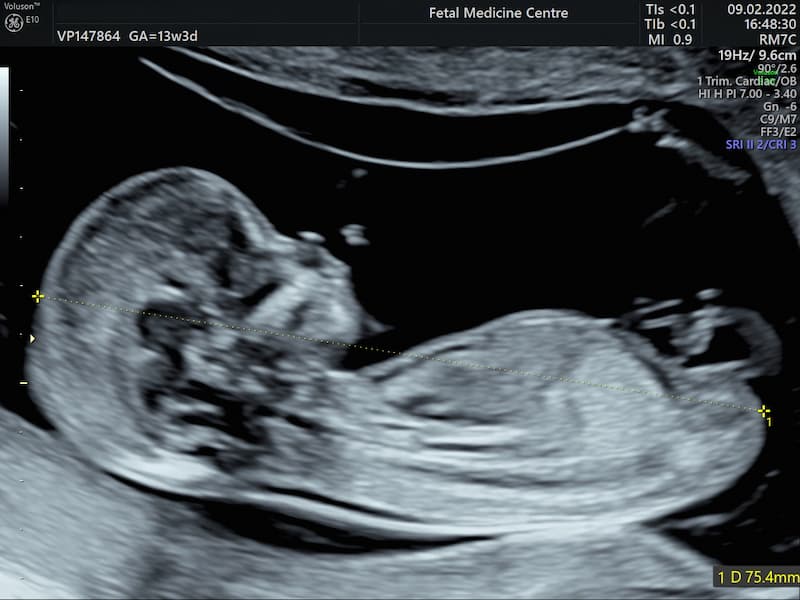

سونوگرافی NT که به سونوگرافی چین پشت گردنی جنین (Nuchal Translucency Ultrasound) نیز معروف است، معمولا بین هفته 11 تا 13 بارداری انجام می شود. در این سونوگرافی، ضخامت مایع پشت گردن جنین (NT) اندازه گیری می شود. افزایش ضخامت مایع پشت گردن جنین می تواند نشان دهنده افزایش خطر ابتلا به برخی اختلالات ژنتیکی مانند سندروم داون باشد. با این حال، نتایج سونوگرافی NT به تنهایی برای تشخیص قطعی هیچ اختلالی کافی نیست و باید با آزمایش خون غربالگری اول بارداری (Combined First Trimester Screening) ترکیب شود.

پزشک زمانی سونوگرافی nt و تعیین جنسیت پسر یا دختر را انجام میدهد که کودک شما بین هفتههای 11 تا 14 بارداری است یا اینکه اندازه جنین 45 تا 84 میلیمتر از بالای سر تا پایین تنه باشد. انتخاب هفته 11 تا 14 بارداری به این دلیل است که مایع پشت گردن کودک پس از این دوران توسط بدن جذب میشود و امکان دارد که بررسیهای ژنتیکی در اوخر بارداری را دشوارتر کند.

تصاویری که از کودک شما بر روی صفحهنمایش ظاهر میشود، مقادیری از مایع پشت گردن را نشان میدهد که اندازهگیری سطح آن براساس میلیمتر است تا با مقادیر نرمال مطابقت داده شود.

چنانچه طول بدن جنین بین 45 تا 84 میلیمتر باشد و میزان مایع اندازهگیریشده در پشت گردن نیز کمتر از 3.5 میلیمتر برآورد شود، در این صورت نتیجه سونوگرافی انتی در محدوده نرمال قرار دارد. این درحالی است که اگر نتیجه اندازهگیری انتی بیشتر از 3.5 میلیمتر باشد، معمولا توصیه میشود که مادران آزمایشهای غربالگری بیشتری را برای این منظور انجام دهند.